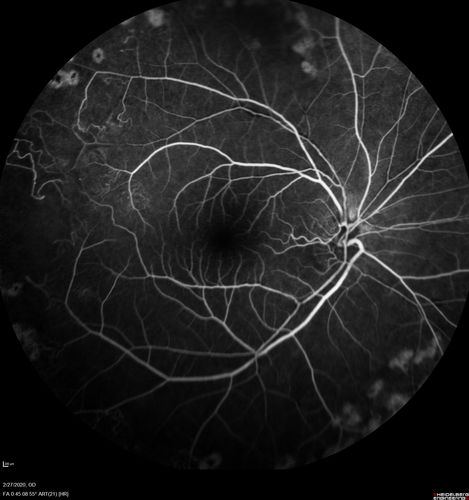

Eales Disease and fresh vitreous hemorrhage - 20 year old man

20 year old mane with fresh vitreous hemorrhage in the right eye.  At age 15 he had a PPV and laser in the left eye and laser in the right eye.  The vision is OD 20/80 PH 20/25, OS 20/25.  The left eye has a mild cataract.  He had prior testing for coagulopathies which was negative.  Testing done for syphillis and TB was negative.  Additional laser was done to prevent further bleeding in the right eye.